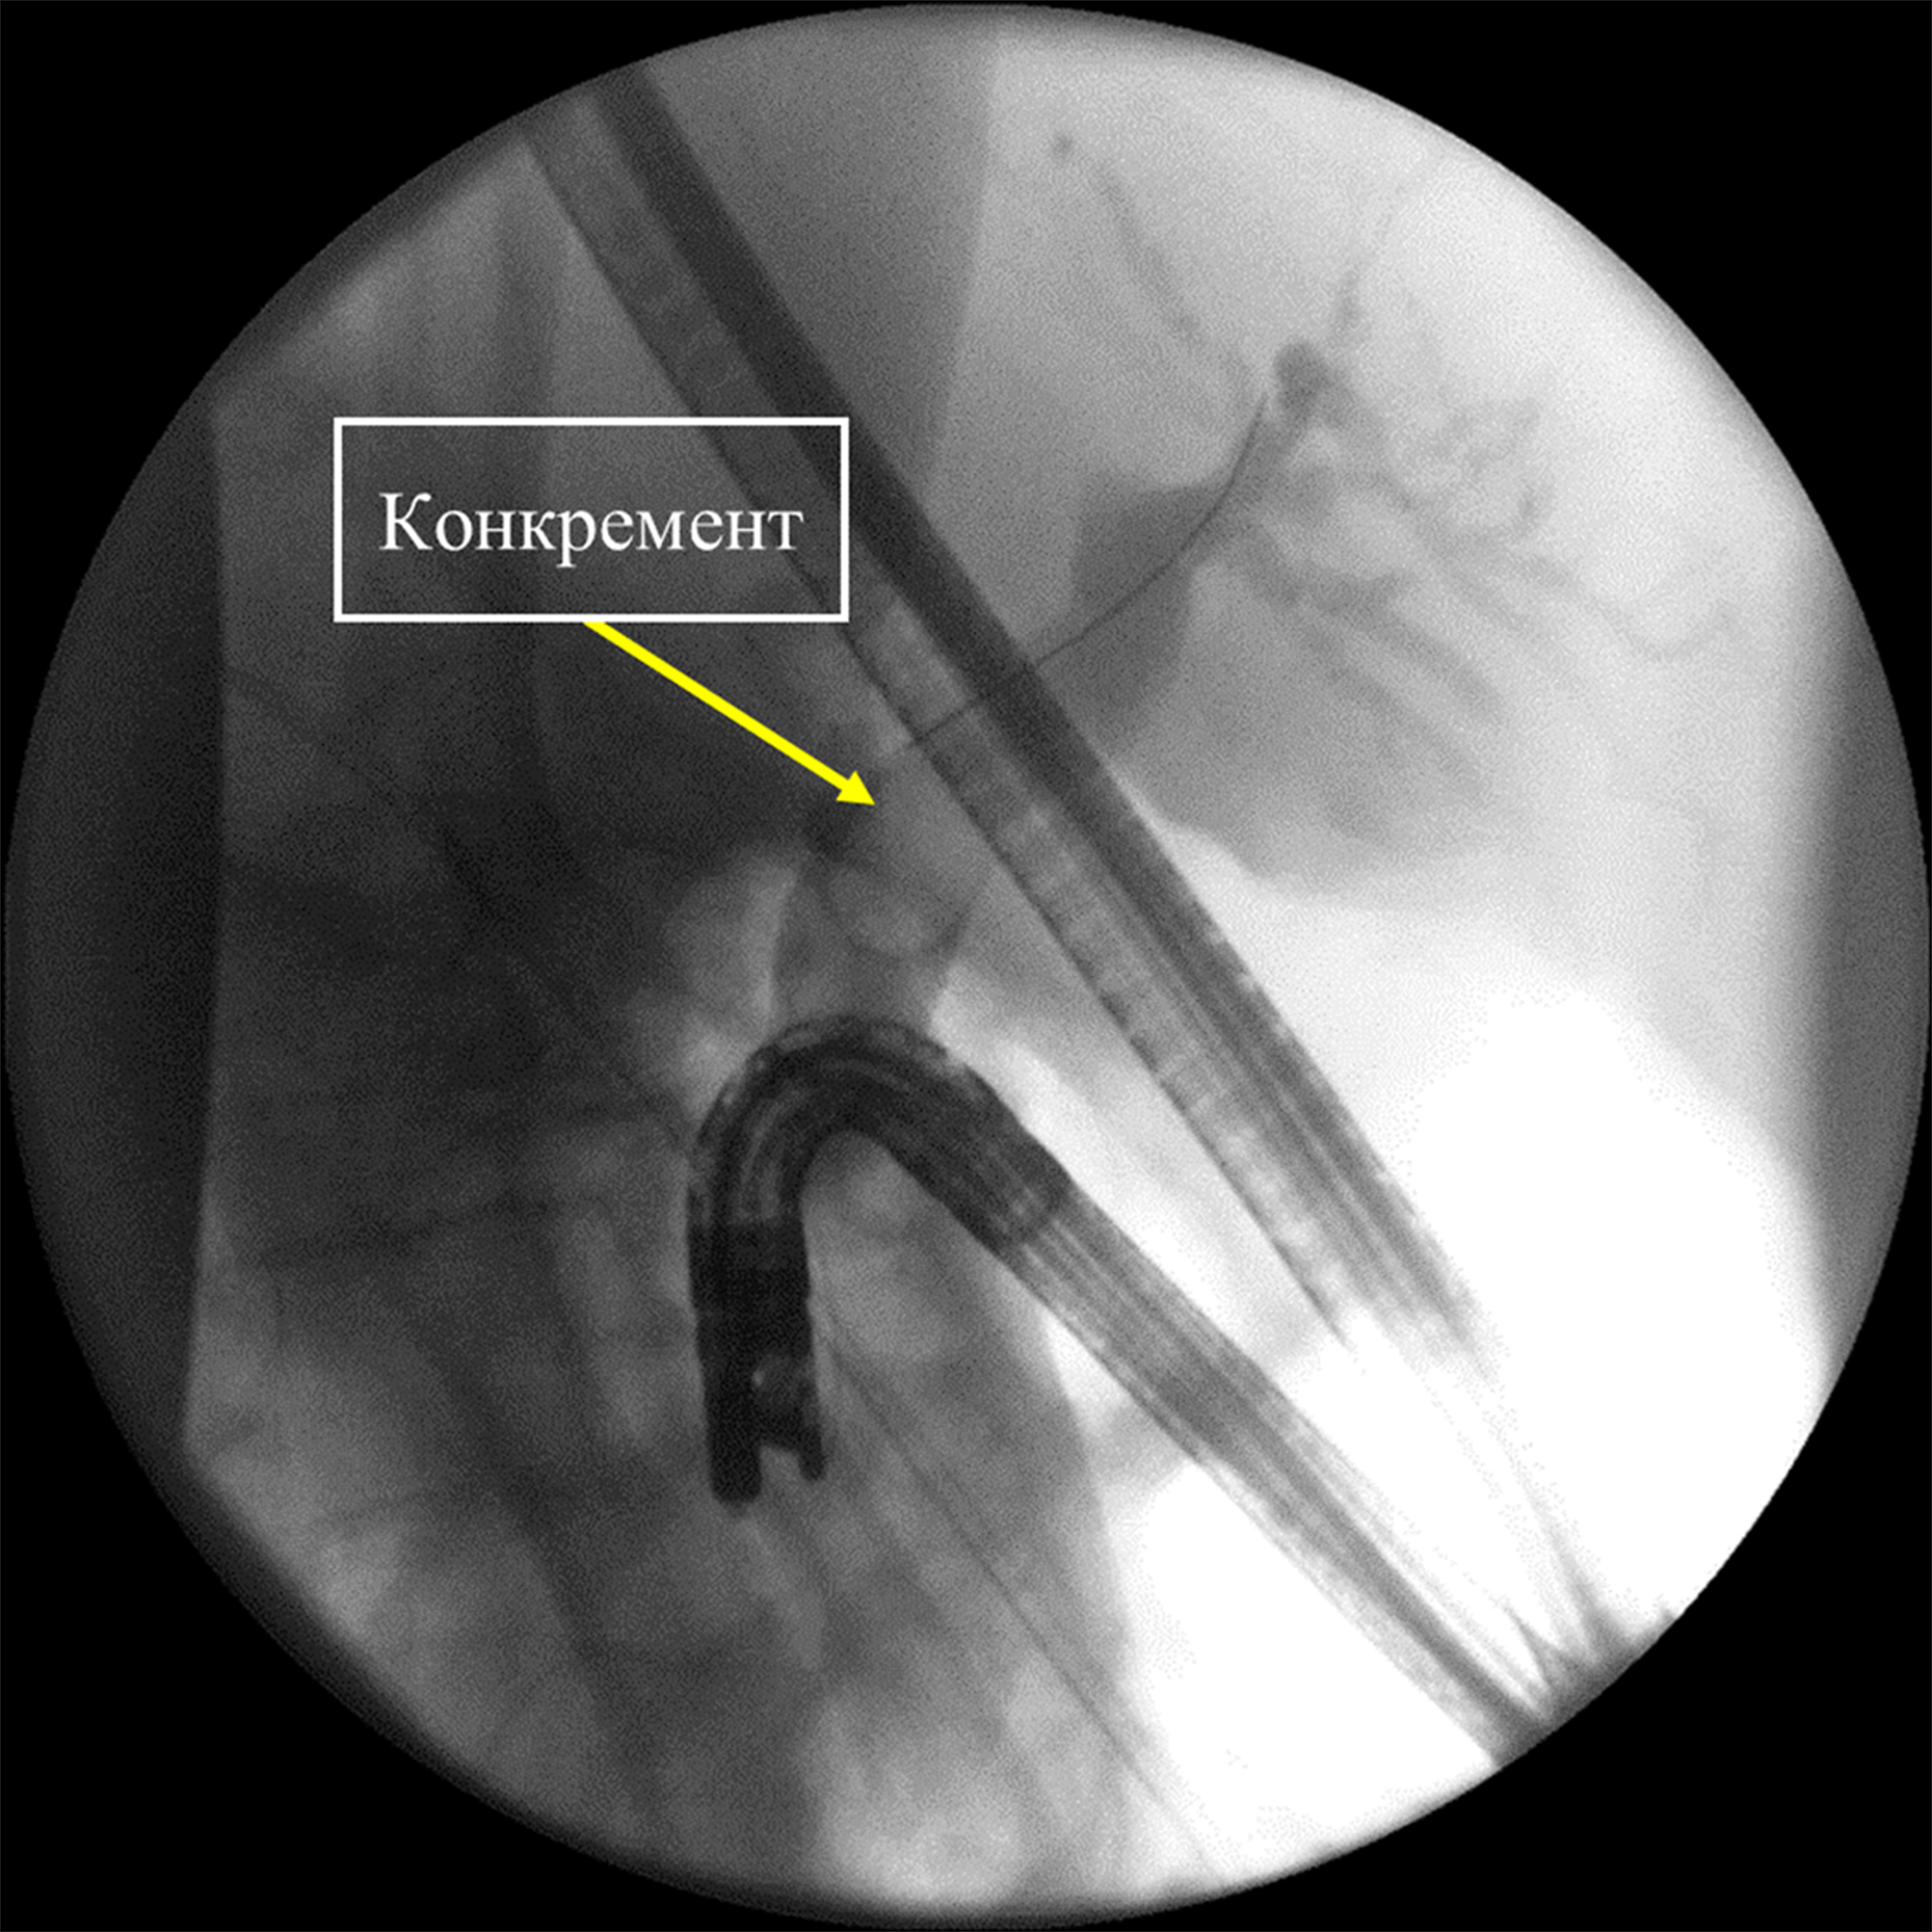

Представлено клиническое наблюдение пациента с желчнокаменной болезнью и так называемым трудным холедохолитиазом. Ввиду развившихся осложнений – механической желтухи и гнойного холангита, а также вследствие большого операционного риска от открытого оперативного вмешательства решено воздержаться. Попытки эндоскопической литэкстракции традиционными способами не увенчались успехом. Выполнены контактная электроимпульсная литотрипсия, литэкстракция. Это позволило устранить холедохолитиаз, восстановить проходимость желчных протоков, ликвидировать холангит и обеспечить возможность безопасного планового оперативного вмешательства по поводу хронического калькулезного холецистита.

Эндоскопическая ретроградная контактная электроимпульсная литотрипсия и литэкстракция